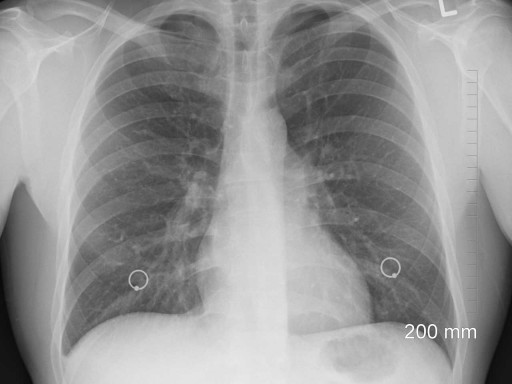

• X ray of lungs with possible asbestos poisoning.